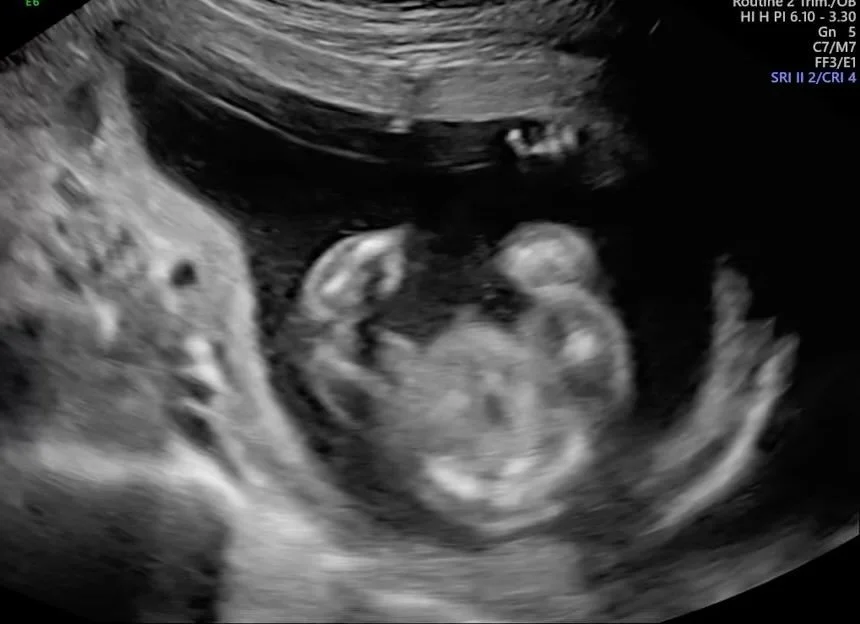

Welcome to Sentiments 4D Ultrasound Studio where beautiful memories begin. Our studio offers a warm, relaxing environment designed to make every visit special and stress-free. With over 10 years of professional ultrasound experience, you can trust that you’re in skilled and caring hands. From early heartbeat scans to breathtaking 3D/4D/HD live imaging, we’re here to help you connect with your baby in the most meaningful way.

In addition to elective ultrasounds, Sentiments offers comprehensive diagnostic obstetric and gynecologic imaging. Our scans are performed with precision, compassion, and attention to detail β€” ensuring you receive accurate results in a comfortable, stress-free environment.